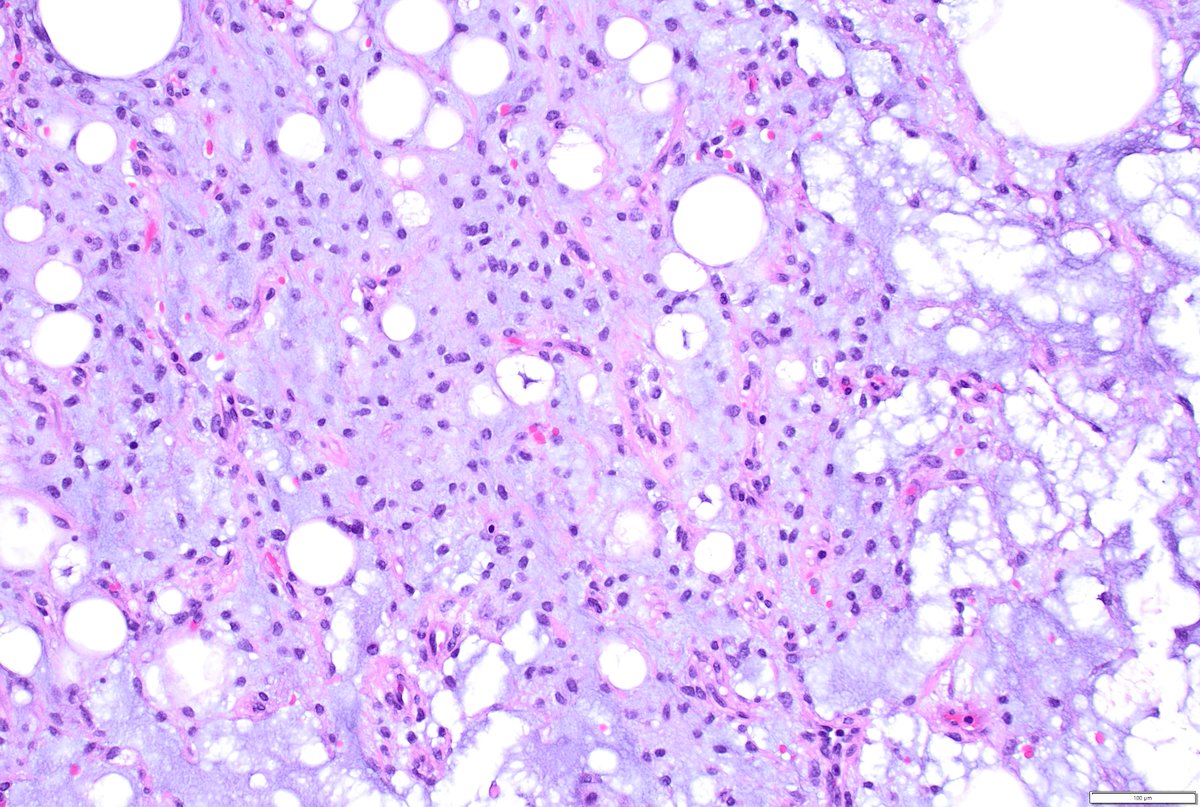

Just out in AJSP – a paper from our group describing a MAJOR new oddity. Tumors that normally arise in the jaw from tooth🦷precursors (ameloblastoma) – but as lung primaries 🫁! This was a neat collaboration b/w MSKCC, Mayo and UTSW where these cases were encountered independently, and we put our heads together with the help of original contributors and fellows to tackle this puzzle. Time will tell if these are truly exceptional or have been underrecognized. journals.lww.com/ajsp/fulltext/… @JLHornick @ENTpathology @MSKPathology @PulmPathSoc @yro854 @thoracicpath @Path_Matt @SansanoValero @AndreMo77438628